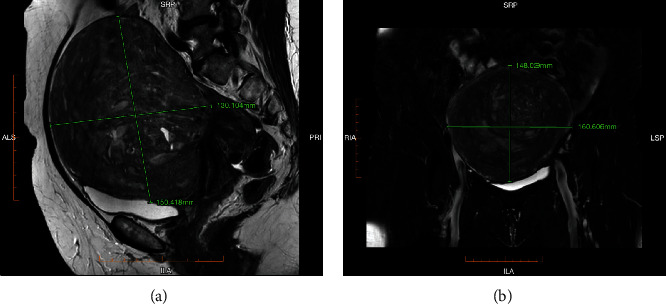

In the context of increased adoption of minimally invasive surgery for benign gynaecological conditions, this study underscores the paramount importance of patient safety. We explored the efficacy of indocyanine green (ICG), a fluorescent dye, in enhancing the visualisation of critical anatomical structures during complex laparoscopic procedures. Our methods involved the direct administration of ICG into the ureters for precise identification and dissection, as well as an innovative vaginal application to delineate the rectovaginal plane in cases with distorted pelvic anatomy. The study presented two cases: a laparoscopic hysterectomy for a multifibroid uterus and a case of advanced endometriosis with rectal involvement. Results indicated that ICG use significantly improved real-time visualisation of the ureters and the rectovaginal plane, which facilitated the surgeries and reduced the cognitive load on surgeons. There were no intraoperative complications, and the postoperative phase showed positive patient outcomes. In conclusion, the application of ICG in these laparoscopic surgeries proved to be a beneficial adjunct, suggesting its potential for broader application in benign gynaecological surgeries. Future research is warranted to explore additional uses of ICG, with a focus on enhancing patient safety and surgical efficacy.